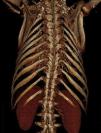

Case reportA 20-year-old male university student living independently, with mandibuloacral dysplasia (a rare autosomal recessive syndrome characterized by premature aging, bone deformities, skin atrophy and lipodystrophy), was referred to our center for severe symptomatic aortic stenosis (peak and mean gradients of 88 mmHg and 60 mmHg, respectively, and functional valve area of 0.7 cm2). He presented symptoms of worsening heart failure, in New York Heart Association (NYHA) functional class III.

He was refused surgical valve replacement by two referral centers due to thoracic deformation with restrictive ventilatory abnormalities and multiple comorbidities, including hypertension, type 2 diabetes, dyslipidemia, bilateral carotid stenosis (50%), thrombosis of the right subclavian artery, obstructive sleep apnea requiring bilevel positive airway pressure (BiPAP) support and proliferative mesangial glomerulonephritis (creatinine clearance 123 ml/min) (Figure 1).